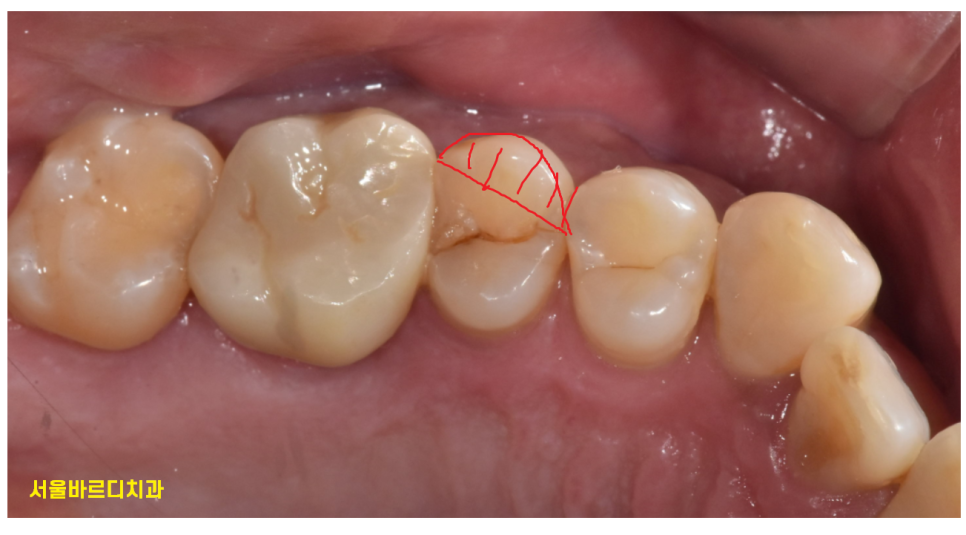

하지만 오늘처럼 치아가 수직으로

도끼로 나무를 내려찍은듯한 형태인 경우

살리기가 힘듭니다.

231102

결국 풍산동 치과에서

발치 후 임플란트 하는 쪽으로 설명드렸는데요.